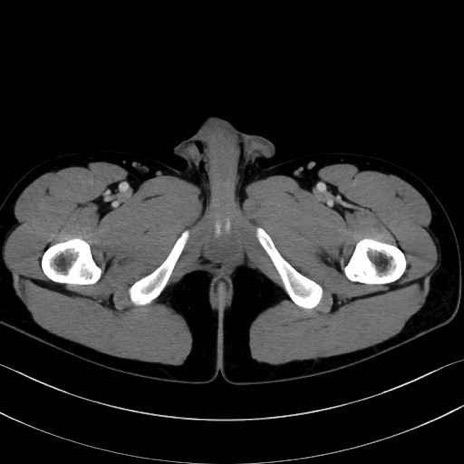

外閉鎖筋 (Obturator externus)